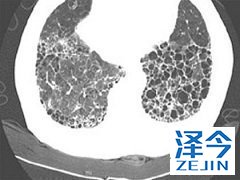

尼达尼布靶向药物抑制能够多种受体 尼达尼布可以用于治疗IPF,有多种靶向,包括受体酪氨酸激酶和非受体酪氨酸激酶。特发性肺纤维化是一种进程性疾病,患者患病后,肺功能会逐渐丧失,还可能出现呼吸困难的症状。那么尼达尼布治疗特发性肺纤维化的效果如何?多种靶向对治疗起到了哪些作用呢?

血管内皮生长因子(VEGF),成纤维细胞生长因子(FGF)和血小板衍生生长因子(PDGF)介导各种过程,包括纤维发生和血管生成,并且涉及IPF的发病机理。通过阻断底物结合和下游信号级联,尼达尼布干扰纤维化中活跃的过程,例如成纤维细胞增殖,迁移和分化,以及细胞外基质的分泌。